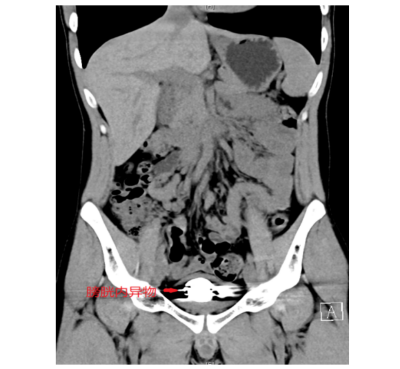

据了解,22岁的简轩(化名)因尿频、尿急、尿痛持续一年,近期症状加重才前往长沙中心立博体育 (南华大学附属长沙中心立博体育 )泌尿外科就医,经影像学检查发现,其膀胱内竟积聚大量直径约5毫米的金属圆珠,排列紧密且表面已形成钙化外壳。该院泌尿外科一区主任傅发军及其团队结合病史及临床经验判断异物为数十颗磁性钢珠,如不及时取出,长期滞留可能导致尿路梗阻、感染甚至组织损伤。

由于异物数量多、磁性强且表面光滑,传统开放手术创伤较大,团队研究后决定采用“经尿道膀胱镜钬激光碎石取异物术”。手术需克服三大难点:磁珠相互吸附难以分离、表面光滑不易抓取、膀胱壁脆弱易损伤。医疗团队通过精准影像定位和精细操作,历时2小时成功取出全部异物,共计50颗磁性钢珠。术后患者症状立即缓解,恢复顺利。